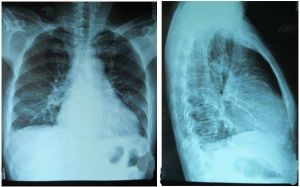

心影增大一般指X線顯示出心臟顯示範圍大於正常範圍,具體方法為自左、右心緣至體中線的最大距離分別為T1、T2,T1+T2=心臟橫徑。心臟橫徑與胸廓橫徑(通過右膈頂水平胸廓的內徑Th)之比即心胸比率。0.50為成人心胸比率的正常上限,0.51-0.55,0.56-0.60及0.60以上分別為輕、中及高度心臟增大。心胸比率受橫膈位置的影響較大,但因此法簡便,成人兒童均適用,仍為目前國內外最常用的心臟測量方法。

三尖瓣隔瓣和(或)後瓣偶爾連同前瓣下移附著於近心尖的右室壁上約占先心病0.5%~1.0%。肺血偏少而心影增大,主動脈和肺動脈影偏小,心影似球囊。

梨形心

又稱二尖瓣型心。肺動脈段凸出及心尖上翹,主動脈結節縮小或正常,狀如梨形。多見於右心負荷或以其為主的心腔變化。常見疾病有二尖瓣病變、房間隔缺損、肺動脈瓣狹...